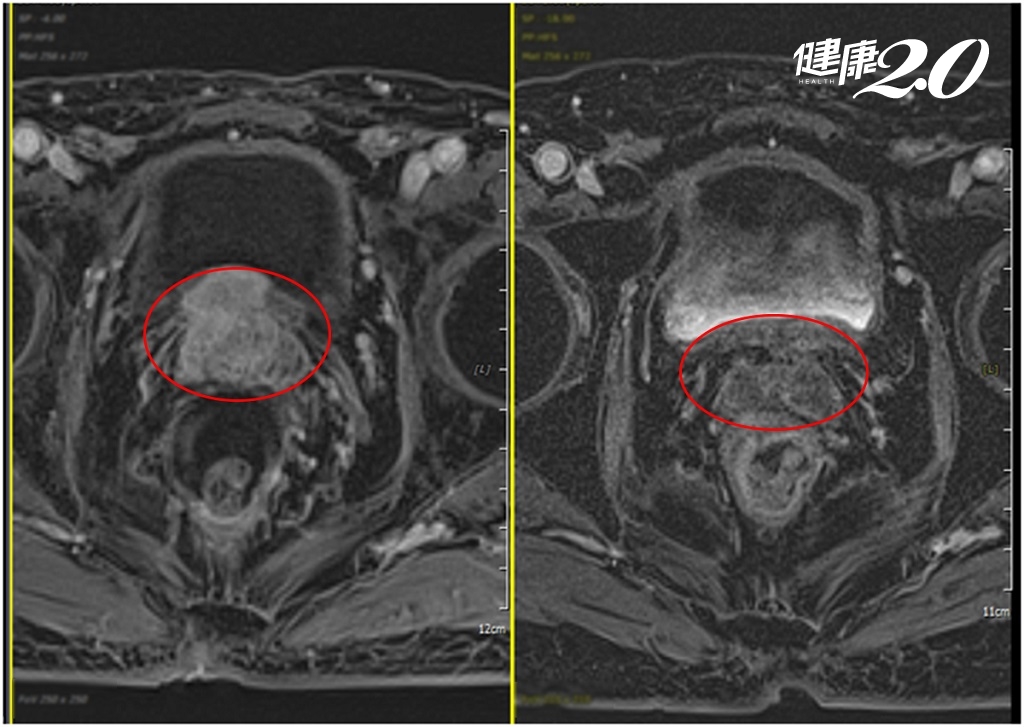

8年過去,老台商的解尿困難更加嚴重,到醫院接受攝護腺切片化驗,竟被診斷出攝護腺癌,癌症指數更高達33.667(正常值小於4)。核磁共振檢查發現,他的攝護腺癌腫瘤大小為2.2公分×1.6公分,已穿透攝護腺表膜並侵犯上方的膀胱。面對這樣的情況,他決定接受抗荷爾蒙治療和快活光子刀放射線治療。

澄清醫院中港院區放射腫瘤科梁家郡醫師表示,這名患者每周接受5次快活光子刀治療,總共進行了42次。完成療程後持續追蹤檢查,今年7月的核磁共振檢查結果顯示,他的攝護腺癌已完全消失,原本被穿透的攝護腺也完整恢復,癌症指數更降到0.025,幾乎驗不到癌細胞的存在。這位老台商慶幸自己命大,決定退休好好享受人生。